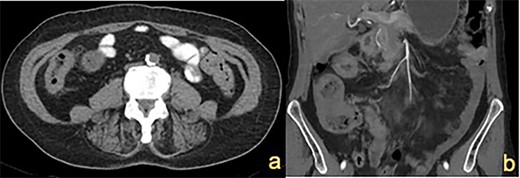

A 72-year-old female presented with abdominal pain and loss of weight. Computed tomography (CT) imaging demonstrated caecal and ascending colon thickening (Fig. 1a). Colonoscopy showed abnormal mucosa in the ascending colon that was unable to be traversed endoscopically (Fig. 2a) and slightly irregular mucosa at the hepatic flexure (Fig. 2b). The appearances were not typical of either a primary colon malignancy or a stricture secondary to inflammatory bowel disease (IBD). Biopsies were non-diagnostic, only showing mucosa with features of regeneration and repair. Given the patient was symptomatic, a laparoscopic right hemicolectomy was performed. Intraoperatively, a thickened firm ascending colon was seen suggesting possible submucosal involvement. Firm nodules were found in the terminal ileum mesentery and proximal transverse colon.

Colonoscopy demonstrating (a) ascending colon lesion, (b) hepatic flexure mucosal abnormality and (c) cobblestoned mucosa in the transverse colon.

CT imaging showed a thickening in the right colon (Fig. 1b). Colonoscopy revealed a stricturing lesion in the hepatic flexure, with abnormal cobblestone-type mucosa without ulcerations or erosions, which transitioned to normal mucosa near the splenic flexure (Fig. 2c). Endoscopic appearances could have represented Crohn’s disease given the cobblestoning but appeared atypical. Biopsies were unable to prove malignancy or IBD but demonstrated fibrosis with features of prolapse or healed ischaemic damage. There were no oestrogen-positive cells.

Colonic metastatic ILC often mimics other pathology in radiological and endoscopic investigations, namely primary colonic malignancy or IBD. On cross-sectional imaging, these lesions can appear as a diffuse mural thickening, with or without circumferential stenosis [7]. The endoscopic appearance is characterized by a multi-nodular cobblestone-like appearance of the mucosa, as shown in our report [8].